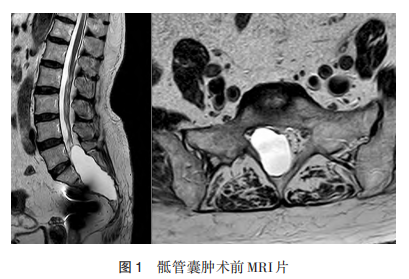

患者,女,69岁,因“腹痛10年,加重半年”入住胃肠外科。既往高血压病史,10年前无明显诱因出现全腹部疼痛,为间断性钝痛,近半年疼痛程度加重,为发作性腹痛,疼痛VAS评分10分,疼痛时大汗淋漓,需用杜冷丁或强痛定才能缓解。病程中无寒颤及发热,无腹泻及便秘,无腰痛及下肢放射痛。入院时体格检查:腹部柔软平坦,腹壁无静脉曲张,腹部无明显压痛,未触及包块;肝脾正常,肋下未触及肝脾;肾区叩击正常,无疼痛;腹部叩诊鼓音,腹部移动性浊音阴性,肠鸣音正常,4次/min,未听到血管杂音。腹部CT检查发现骶管囊肿,骶椎椎管扩张,局部骨质变薄。在胃肠外科予以保护胃黏膜、通便等药物治疗后效果差,进一步胃肠镜检查结果:慢性萎缩性胃炎(胃底黏膜),活动性(+),腺体萎缩(++),肠上皮化生(+);乙状结肠黏膜低级别管状腺瘤(Ⅰ级)。胃肠外科进一步治疗后患者症状仍无改善,转入脊柱脊髓外科治疗。再次体格检查:骶尾部轻压痛,轻叩痛,无下肢放射性疼痛,会阴区皮肤感觉略减退,下肢肌力感觉正常。骶椎MRI显示骶椎囊肿,L5~S4层面椎管内可见囊状长T2信号影,边界清晰,最大截面3cm×4cm,上下径约8.9cm,骶椎受压变形(图1)。

采用气管插管全身麻醉,取俯卧位,腹部悬空。取骶尾部后侧正中切口,逐层分离至骶骨椎板,显露骶骨椎板,将S1~S3椎板完整切除并保留,切除L5部分椎板。显露椎管内组织,显微镜下钝性剥离囊肿,充分显露囊肿组织,探查囊肿近端的位置,进一步确定其与硬脊膜之间的关系,确定囊肿近端开口。切开囊壁后有脑脊液样液体流出,探查囊肿内可见S2神经根(右侧),显露囊肿的漏口并严密缝合,避免脑脊液漏,然后将囊壁进一步缝合成形,包裹在神经周边形成袖套样,用4-0可吸收线缝合固定,检查神经根避免其外露。完整切除囊肿,取标本送病理检查,切除囊肿后出现囊肿的残留空腔,为了预防囊肿复发,需取自皮下脂肪瓣填塞残留空腔。将取下的骶椎椎板重新复位,选用合适的钛板固定椎板。彻底冲洗,切口内留置2根引流管,逐层缝合肌肉、皮下组织、皮肤。术后保持俯卧位,切口处用盐袋压迫预防脑脊液漏及皮下积液,根据引流量决定拔除引流管时间。术后复查腰椎MRI及CT显示椎间盘囊肿已清除,椎板固定良好(图2、3),病理检查结果明确了骶管囊肿的诊断。术后1年MRI显示骶管内脂肪填充(图4),未再出现腹痛症状,未见囊肿复发。